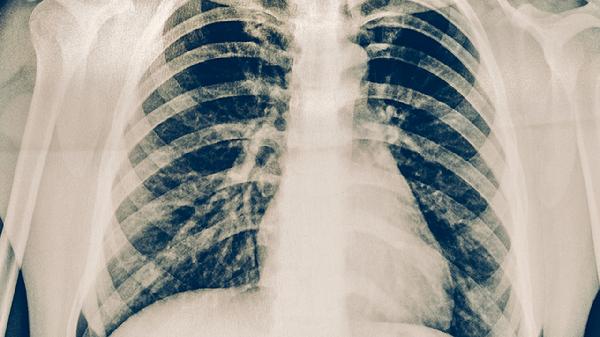

肋间神经炎肌电图可能显示神经传导异常,MRI可发现神经根受压。肋软骨炎X线多无异常,超声或MRI可见肋软骨增厚水肿,实验室检查可能显示炎症指标轻度升高。